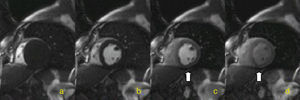

A perfusão do miocárdio é avaliada por RM em sequências ponderadas em T1 com imagens dinâmicas aquando da administração rápida de quelato de gadolínio por via endovenosa (Figura 1).

Os exames de RM foram realizados num aparelho Siemens Symphony Maestro Class 1,5 T. Em todos, efetuámos avaliação de duas «passagens» (em stress e em repouso) e pesquisámos o realce tardio do miocárdio. A sequência utilizada para o estudo de perfusão é ponderada em T1, «SSFP» com pulso de inversão (ângulo de báscula de 15°, tempo de inversão de 100 ms, tempo de eco de 1,11ms, tempo de repetição de 182ms; matriz de 78 x 128 pixels), com obtenção de quatro imagens (três no eixo curto cardíaco e um no eixo longo) por batimento cardíaco ou por 2.° batimento cardíaco (dependendo da frequência cardíaca).

A adenosina foi administrada em infusão durante 4 minutos a uma dose de 140μg/kg/min. Os estudos de perfusão foram efetuados após a injeção por via endovenosa de quelato de gadolínio a um fluxo de 4ml/s e a uma dose de 0,10 mmol/kg. Em todos os doentes, avaliámos a função ventricular esquerda.